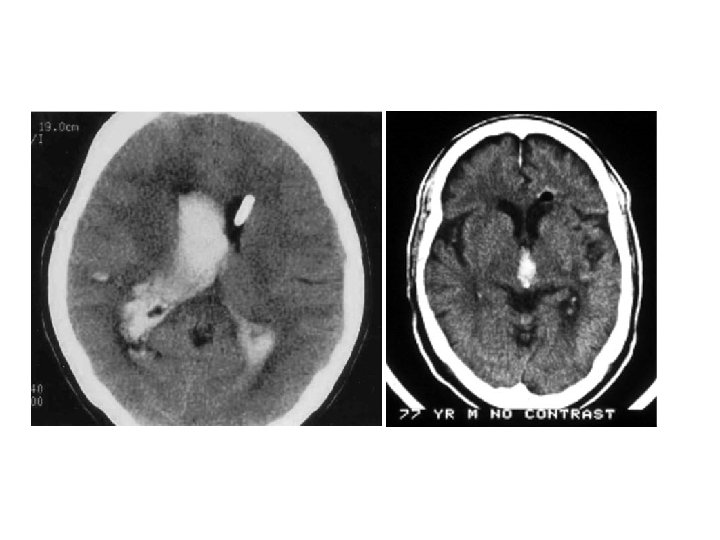

陰性 ↓ 1. Blood cultures (x 3), 2. Ischemic stroke evaluation, 3. Coagulopathy evaluation, 4. MRI c/s gadolinium, 5. Consider cerebral angiography • 血管攝影是一種侵襲性的檢查。 • 血腫的大小是評估預後最好的 具。 • Volume: estimated from CT ( A x B x C) / 2 A = the greatest diameter of hematoma B = the diameter perpendicular to A C = the thickness measured as the number of CT slices where the hematoma is visualized multiplied by slice thickness.

Hemorrhage Volume-Mortality • Volume graters 60 cm 3 – Deep-93% – Lobar-71% • Volumes 30 -60 cm 3 – Deep-60% – Lobar-60% – Cerebellar-75% • Volumes less 30 cm 3 – Deep-23% – Lobar-7% – Cerebellar-57% Broderick: Volume of ICH; Stroke Vol 24, No 7

ICH Hemorrhage Volume • Old concept-Hemorrhage static process; bleeding complete in a minutes • New concept-Hemorrhage is dynamic; process continues for several hours

• Hematoma enlargement or hematoma growth - increase in the volume of hematoma, can occur several hours after stroke onset, frequently associated with neurologic deterioration (66%). * initial CT scan < 3 hrs (35%) * at 3 – 6 hrs (16%) * at 6 – 12 hrs (15%) * at 12 – 24 hrs (6%) - Predisposing factors: history of brain infarction; liver disease; high blood glucose ( >141 mg/dl) or Hb. A 1 C ( >5. 1%); high systolic

blood pressure ( > 200 mm Hg). - Predictors: short time interval between onset and admission; habitual alcohol consumption; consciousness disturbance; an irregularly shaped hematoma shown on initial CT scan; and low levels of fibrinogen. • Outcome - mortality rate from ICH decreased dramatically due to: * increased detection rate of milder ICH. * decrease in the prevalence of HTN. * improved antihypertensive therapy.